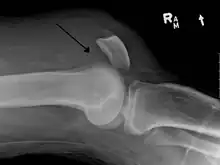

X-ray of a tear of the patellar tendon. On the left: The kneecap is pulled up. On the right: Significant dent in the soft tissue above the kneecap.